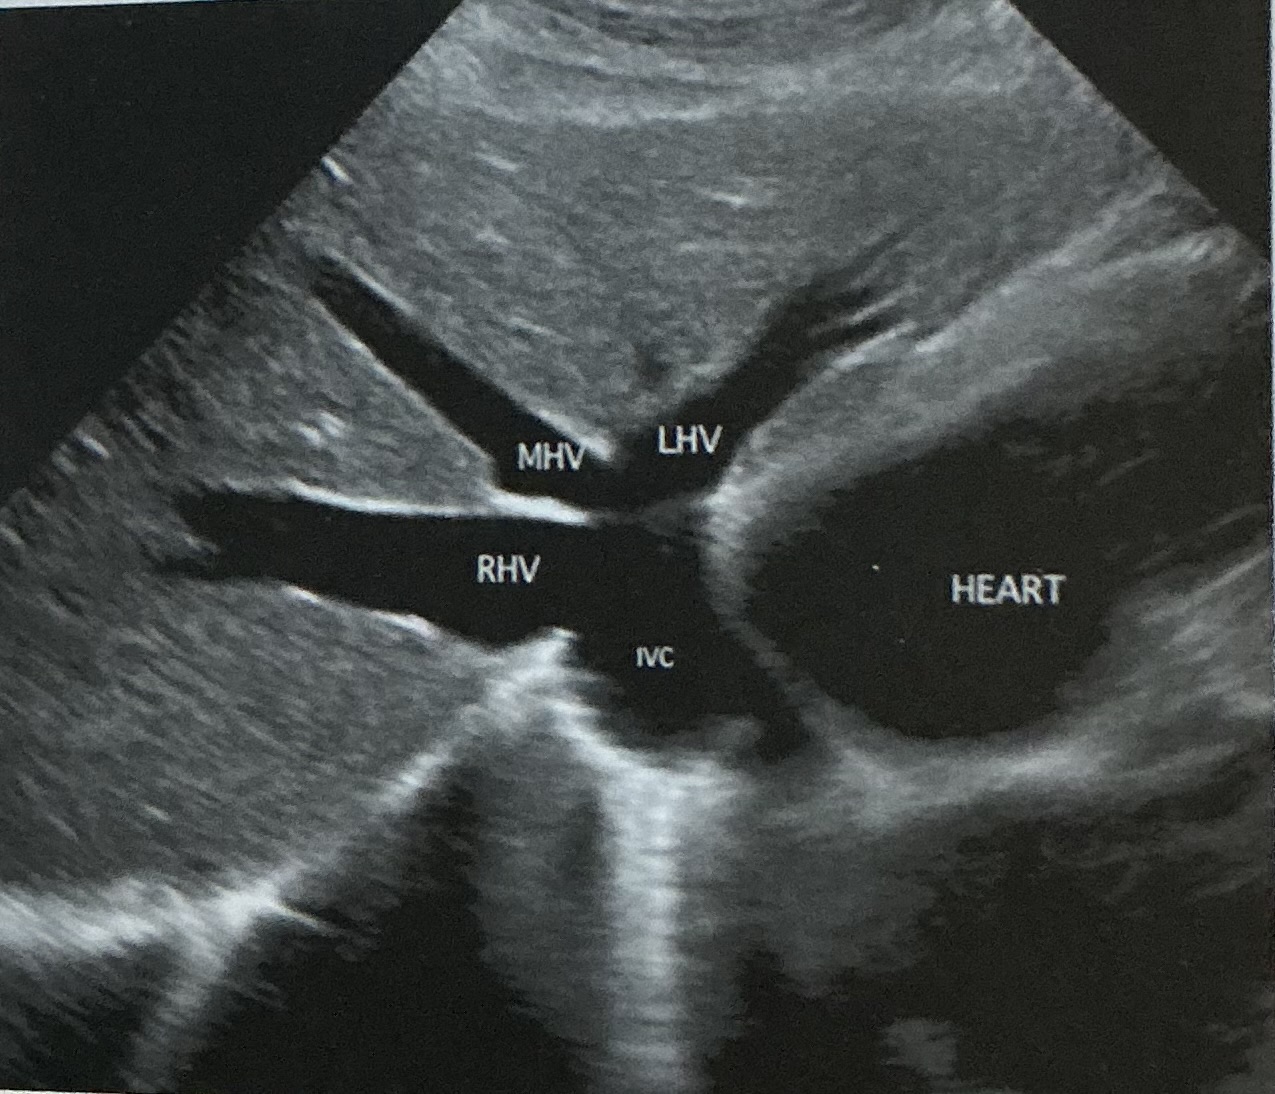

Label this picture

what sign is it depicting

Why does this happen?

What sign does the hepatic veins normally depict?

Canadian moose sign

Dilatation from right heart failure

Playboy bunny sign